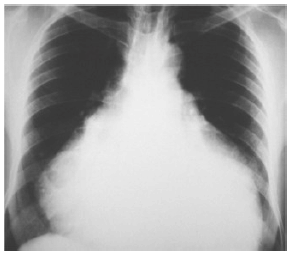

Paciente de 45 anos, sexo feminino, admitida em unidade de pronto atendimento com queixa de dispneia progressiva há 2 dias, com piora significativa até os mínimos esforços. Nega outros sintomas. Antecedente de neoplasia de mama, em acompanhamento irregular. Nega outras comorbidades. Nega uso prévio de medicações. Ao exame físico: vias aéreas aparentemente pérvias; frequência respiratória 26ipm, tórax com movimentos simétricos, murmúrio vesicular rude bilateralmente, som claro pulmonar a percussão, saturação periférica de oxigênio 88%; bulhas rítmicas e hipofonéticas, frequência cardíaca 120bpm, pressão arterial 70x40mmHg, pele fria, pegajosa, com tempo de enchimento capilar lentificado, turgência jugular evidente; aparente redução da amplitude do pulso e pressão arterial sistólica durante a inspiração; abertura ocular a estímulos dolorosos, emitindo palavras desconexas e localizando estímulos dolorosos, pupilas isofotorreagentes, sem déficit motor evidente. Trouxe radiografia de tórax realizada ontem em unidade primária de saúde (representada a seguir). Iniciado reposição volêmica com solução isotônica por acesso venoso periférico.